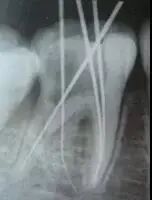

1、 开髓 洞型是否制备的符合要求,髓室顶是否揭得刚刚好,没有破坏洞壁及洞底结构。 图1、裂钻钻到近髓 图2、球钻穿髓 图3、小号锉探查根管口 图4、球钻揭髓顶 图5、修整洞型 图6、完成开髓 2、 去腐 根管预备之前是否将窝洞的腐质完全去除,避免在根管预备过程中将冠部污染带进根管; 3、 根管口的直线通道 特别对于弯曲根管!预备根管之前是否重视这个环节,尽管找到了根管口,锉也能顺利进入根管,但根管口的直线通道是否建立也是衡量医生操作技能的重要依据。方法很多:手动器械操作时我们可以采用价格便宜的“GG”钻,PROTAPER 机动预备时可以采用 SX 锉。 1、弯曲根管冠部处理之前; 2、用GG钻或SX锉进行预备; 3、处理后形成的直线通道 我的病例1_____冠部处理成直线通道后的充填效果 我的病例2_____下颌7"C"型根管的充填效果 4、 疏通中下段根管 要用小号锉 08和10号 K锉进行探查,手法是用顺反30度来回搓动的方法进入,建立根管中下段的预备通道,然后换用15号 K锉进行疏通,便于大号不锈钢器械或镍钛器械的进入。 5、 确定工作长度 15号 K锉进入时最好配合根测仪;术前,术中,术后都要拍X—RAY。 6、 冲洗方法 每次换锉之前及都要进行,但是否有效往往是不确定的,因为冲洗的效果和多方面因素有关——小号的针头(如果没有专用的针头可以用皮试的小针头),“双次冲洗法(自命名)”——即每次冲洗完毕后再用小号锉(如10号或15号)进入根管下段捣动一番,让碎屑随着冲洗液浮出根管中上段,然后进行二次冲洗,这样就能将根管内的碎屑清除彻底!注意头次冲洗后不要清除根管内的冲洗液,它的存在有非常重要的作用! 7、 建立根充档 根尖部牙本质和牙骨质的交界处不要破坏,这对后期的根充以及主尖的选择很有意义,前提是每次预备都要明确的把握工作长度! 8、 弯曲根管最好采用不锈钢锉同镍钛锉配合使用 用不锈钢器械预备弯曲根管中下段,镍钛器械预备中上段! 9、 "冠根方向”预备是可取的方法,但有些时候还是需要结合“逐步后退法"使用的。 10、 熟悉使用器械的性能及各类操作方法的临床要点 逐步后退法预备存在的一些问题——A,根管锉与根管壁接触面积大(锉进入时困难;容易被卡住;器械容易折断;碎屑容易被推向根尖区;锉尖不好控制。);B,根管成形受限(根尖区冲洗困难;碎屑清除困难;碎屑容易推出根尖孔以外引起根尖症状。)C,需要频繁换锉(操作繁琐;临床操作时间长。)因此,很多牙医已经不采用该法,取而代之使用的是采用镍钛器械进行冠根向预备法“Crown Down”。但不锈钢器械(如K锉)还是有它的用途——小号K锉可以用来寻找根管以及进行根管疏通;用来确定工作长度;用来进行根尖预备;弯曲根管配合镍钛器械进行预备比较安全! 问题答案:这个病例的问题主要反应在开髓的洞形修整,注意观察该牙X-RAY的左侧洞壁,如果常规情况制备成这样是由于裂钻破坏了洞壁和洞底所形成的台阶。如果评估根管治疗的质量那是要扣分的!但这个病例仔细观察洞壁形态就可以看出:该病例属于再治疗的病例,因此还是属于一个理想的病例。 图文来源网络,版权属于原作者 转载只为分享,如有侵权,请联系删除 扫一扫 | 客服微信 了解更多 | 行业招聘资讯 - 医招职达 - 让人才更有价值 做精准高效的口腔人力资源服务平台

最后来玩一个根管治疗质量的评估——下图是武大彭彬教授的一个病例,仔细观察可以挑出一点问题,但问题事出有因!看看你的“眼力”如何——问题在哪里?教授的专业水平是不用怀疑的,那么事出的原因可能是什么?